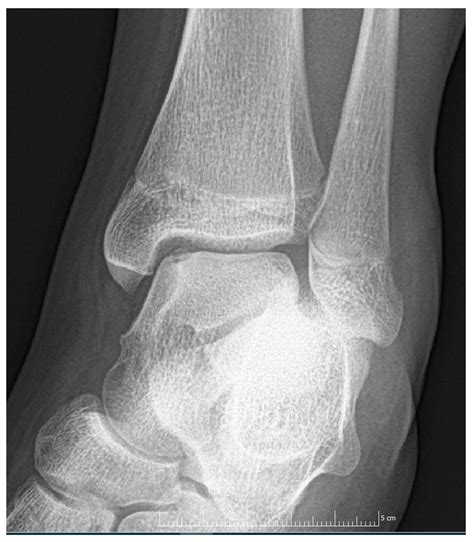

• Imaging Tests: Imaging tests, such as X-rays, MRI, or CT scans, are used to visualize the bone and cartilage within the ankle joint. These tests can help identify the location and extent of the lesion.

Imaging tests are particularly important in diagnosing Osteochondritis Dissecans Ankle, as they can provide detailed information about the condition of the bone and cartilage.